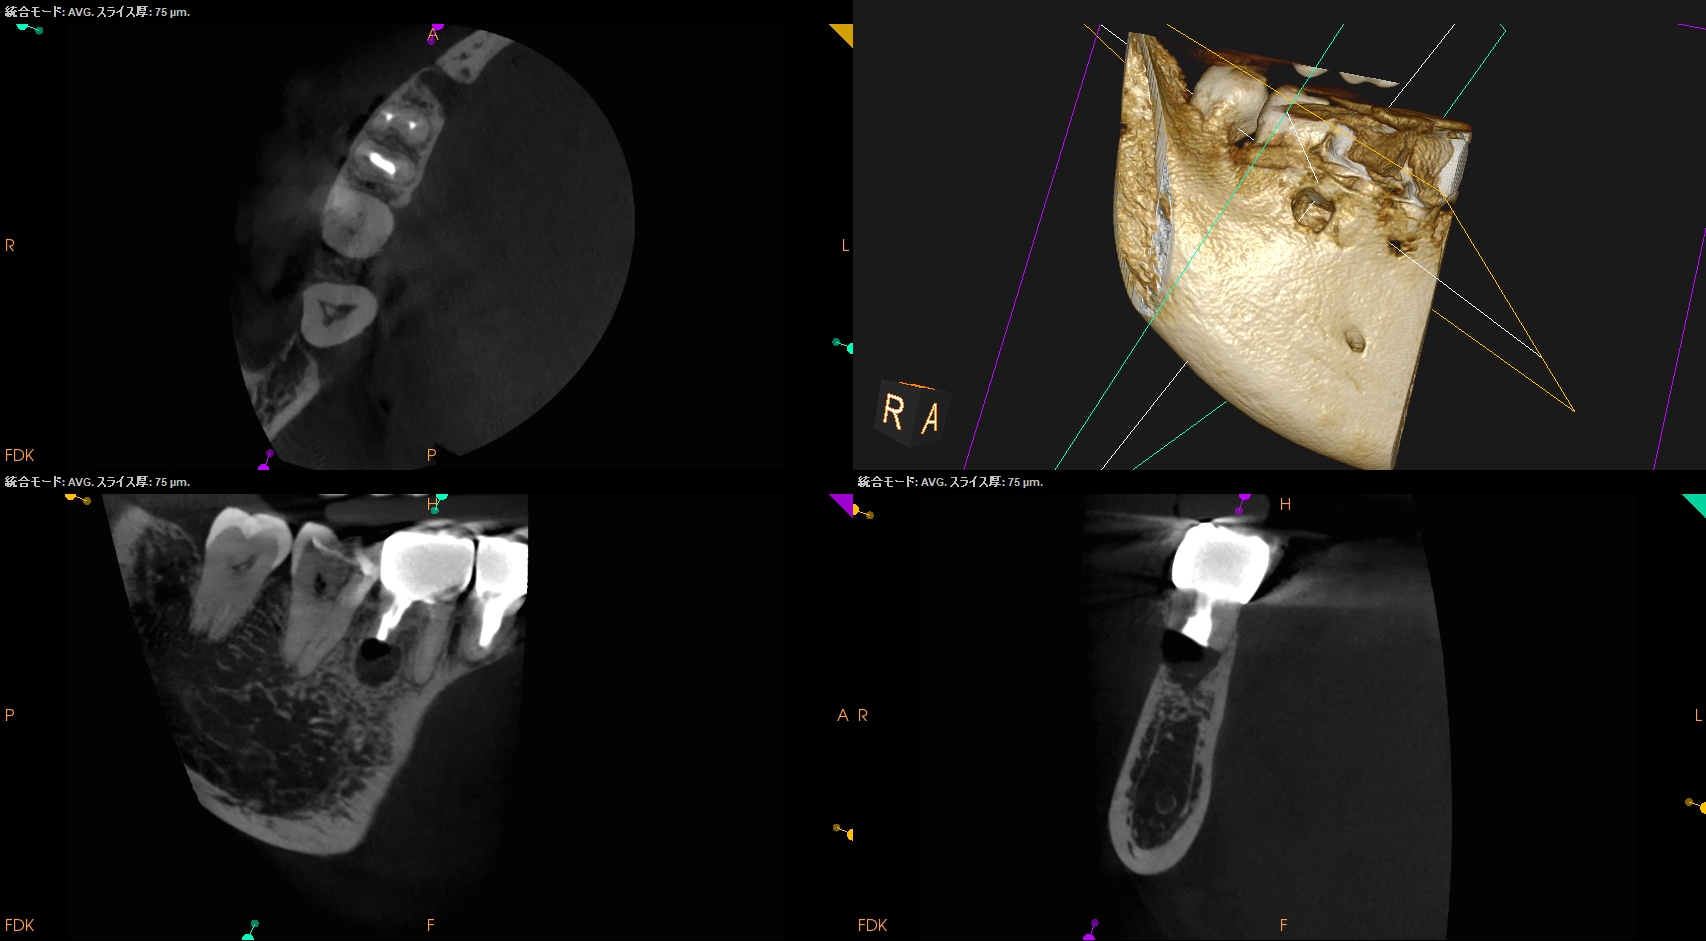

#30 D Apicoectomy(2025.10.8)

私にはD根が歯槽骨から透けて見える。

OsteotomyしてRoot resectionした。

Retroprepした。ここが一番時間がかかる。

逆根管充填した。

PA, CBCTを撮影した。

問題はないだろう。